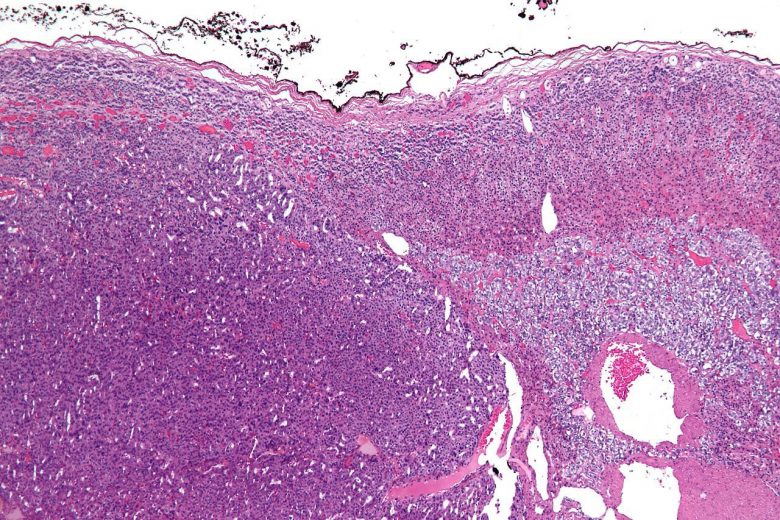

Image Credit: Lance Liotta Laboratory / Wikimedia Commons.

Adrenocortical cancer

“Adrenocortical carcinoma is a rare disease in which malignant (cancer) cells form in the outer layer of the adrenal gland… Having certain genetic conditions increases the risk of adrenocortical carcinoma.

“Symptoms of adrenocortical carcinoma include pain in the abdomen… Imaging studies and tests that examine the blood and urine are used to detect (find) and diagnose adrenocortical carcinoma. Certain factors affect the prognosis (chance of recovery) and treatment options.”